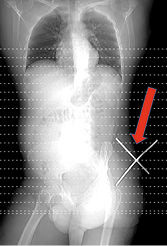

Bei Ankunft im Schockraum um 11:36 Uhr war der Patient schmerzfrei. Es erfolgte die Übergabe des Patienten an das Schockraumteam. Im Rahmen der unmittelbar nach Ankunft des Patienten im Schockraum durchgeführten Sonographie konnte das Vorliegen freier intraabdomineller Flüssigkeit sowie Verletzungen von Milz und linker Niere zunächst ausgeschlossen werden. Ein in der weiteren Folge durchgeführtes kontrastmittelgestütztes Spiral-CT von Thorax und Abdomen ergaben folgenden Befund: „Oberhalb der linken Beckenschaufel Eintritt des Stahlbetongitters mit Ausdehnung bis in den Musculus obliquus externus links mit umgebenden Lufteinschlüssen ohne Hämatombildung oder venöses Pooling“ (   Abb. 2 ).

Der Patient blieb weiterhin kreislaufstabil, es erfolgte unmittelbar anschließend die operative Entfernung des Stahlstabes in komplikationsloser Allgemeinanästhesie sowie die Gabe von Cefuroxim i.v. Der Patient konnte bei komplikationslosem postoperativem Verlauf bereits drei Tage später in gutem Allgemeinzustand nach Hause entlassen werden.